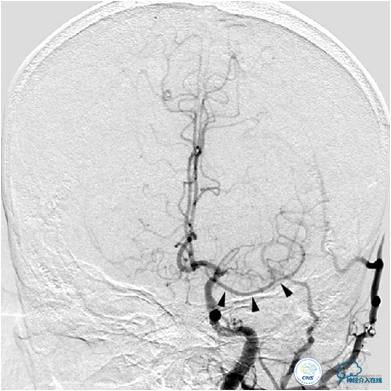

患者入院后,完善颅内CTA(图1)及血管造影(图2~3)检查,发现右侧颈内动脉颅内段闭塞,右侧大脑前动脉依靠左侧颈内动脉系统通过前交通动脉供血,右侧大脑中动脉供血区则依赖于右侧大脑前动脉(ACA)软脑膜代偿供血,左侧大脑中动脉闭塞,依靠一少见血管代偿供血,该血管起自左侧大脑前动脉A2段起始部,代偿供应左侧大脑中动脉供血区。由于该患者灌注CT(图4)未见明显低灌注区,遂给予患者抗血小板、降脂及控制危险因素治疗出院。出院后电话随访未再出现过上述症状。

图3A:左侧颈总动脉造影动脉期,看到异常血管代偿供应左侧大脑中动脉分布区(箭头),双侧大脑前动脉双干显示。